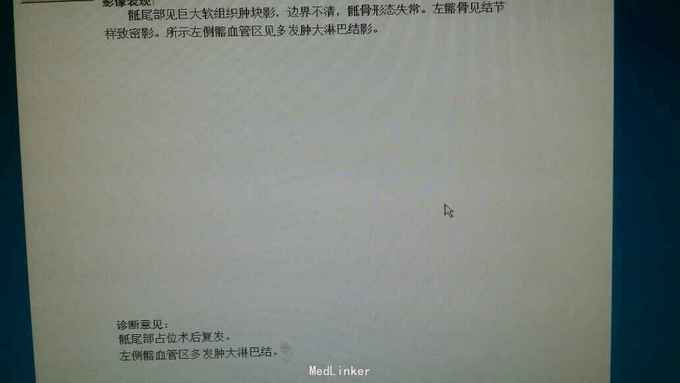

查体:骶尾部一长约20cm术后瘢痕,可触及大小约15cm*15cm质韧包块,活动性差,压痛明显,周围皮温升高。 辅助检查:平扫加增强磁共振回示:骶尾部肿瘤术后改变,双侧臀部及双侧臀大肌,肛管右侧软组织异常信号,考虑肿瘤复发。CT见图。